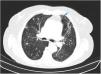

En busca de la aspergilosis

In search for aspergillosis